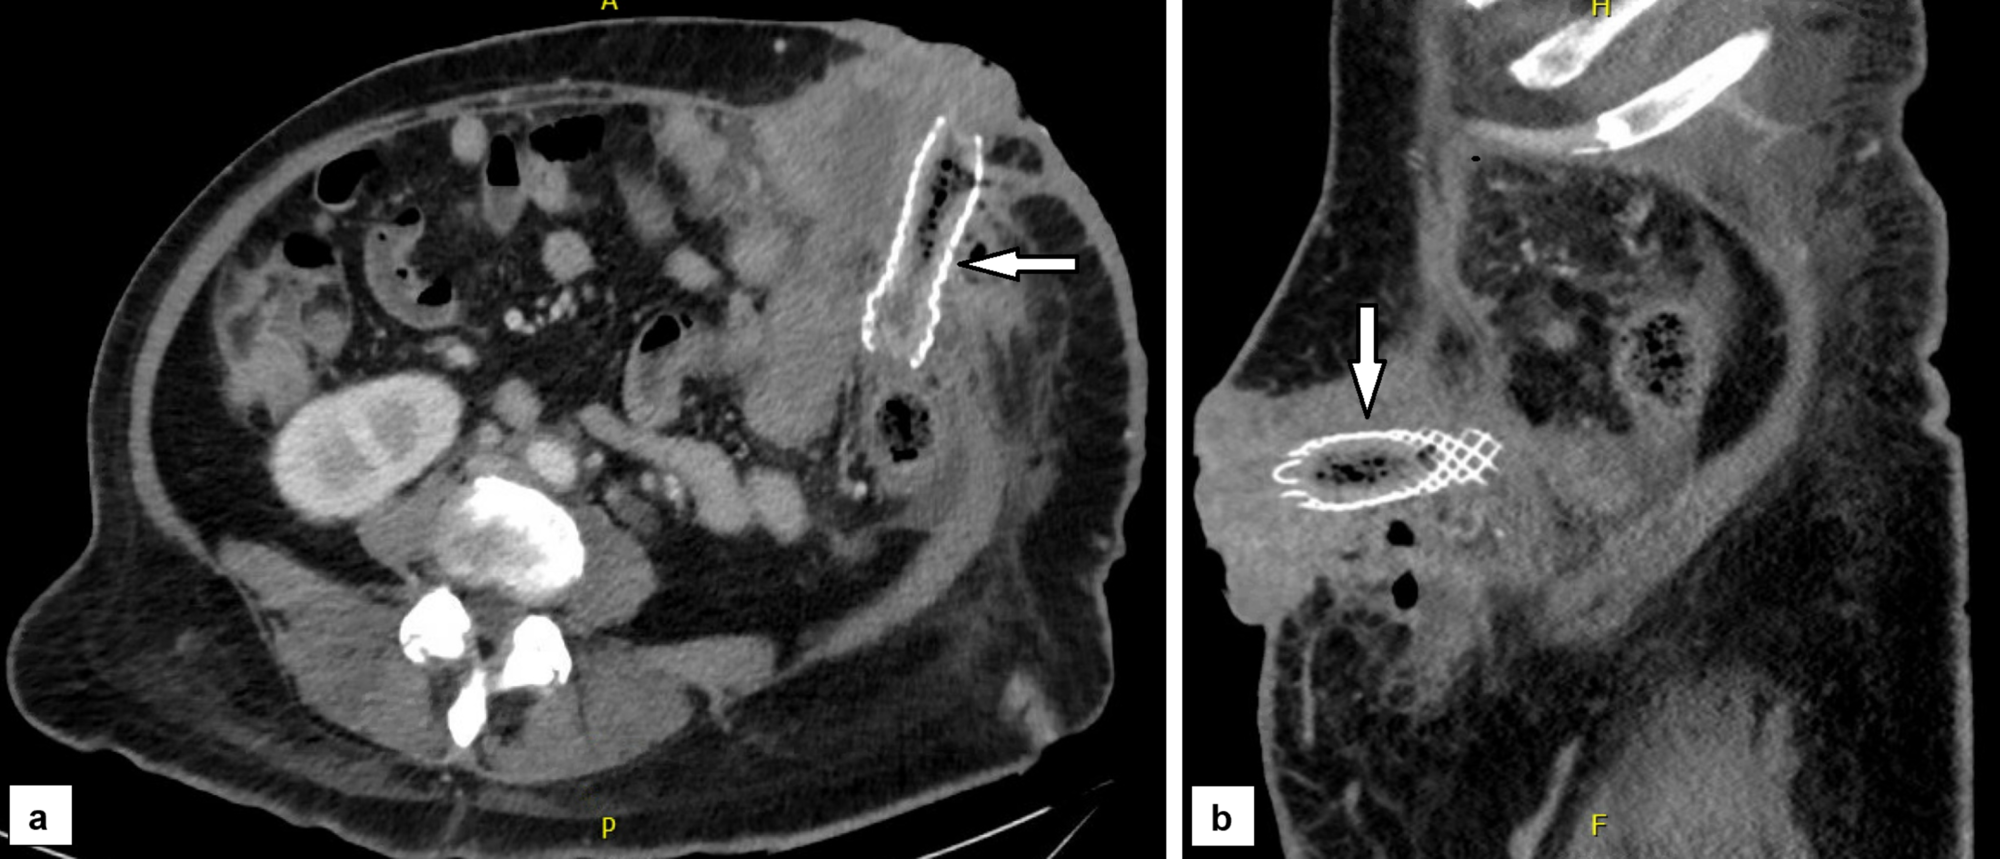

From www.cureus.com

Cureus Metal Stent Insertion for Malignant Obstruction of a Colostomy Ct Scan Metal Therefore, leave the following at home: a ct scan takes pictures of your: metal affects ct images. engineers at johns hopkins have solved the problem of distorted imaging scans that plague surgeons who need to use them to assess the. metal objects including jewelry, eyeglasses, dentures and hairpins may affect the ct images and should be. Ct Scan Metal.